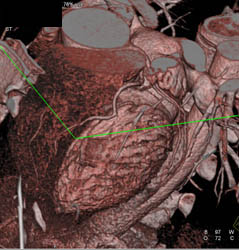

Diagnosis

Normal RCA